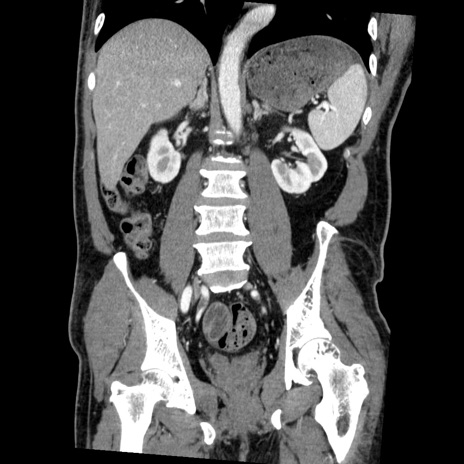

症例22(冠状断像)

【症例】50歳代男性

【主訴】腹痛

【現病歴】AVMからの被殻出血のため回復期リハ病棟入院中。 本日午後3時頃急に下腹部痛が出現した。

【既往歴】AVM、被殻出血、虫垂炎、高血圧

【身体所見】意識晴明、左半身不全麻痺、会話の理解は良好、36.5°C、腹部:膨隆、全体に板状硬、下腹部正中に圧痛点あり、反跳痛-、筋性防御不明、右下腹部にope scar

【データ】WBC 9400、CRP 0.06